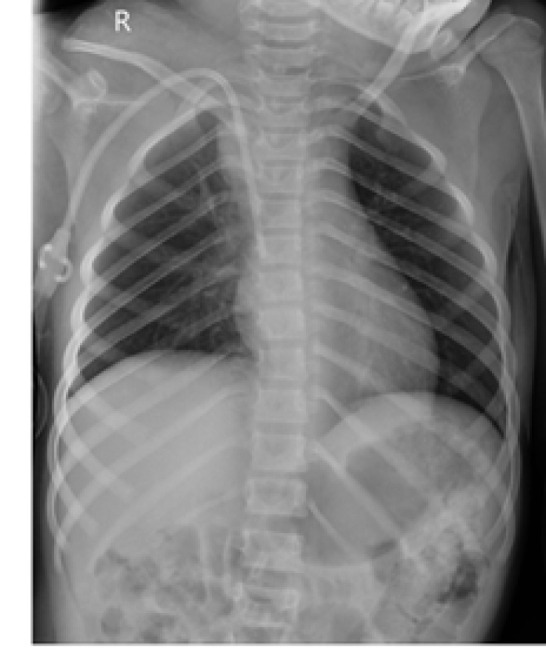

Horner syndrome, characterized by the triad of unilateral ptosis, miosis, and anhidrosis, typically arises following a stroke, surgical interventions in the neck and chest, or trauma. Horner syndrome is rare in children. This study presents the case of a 9-year-old girl with End-Stage Renal Disease (ESRD) caused by renal hypodysplasia. After permcath insertion, she developed a severe headache and anisocoria, followed by ptosis and a progressively expanding neck hematoma. Physical examination and MRI of the neck revealed that Horner syndrome, caused by hematoma formation following permcath placement, was the diagnosis. Supportive interventions were implemented, leading to significant improvement in Horner syndrome over a six-month period. Complications from permcath insertion can be a cause of Horner syndrome.